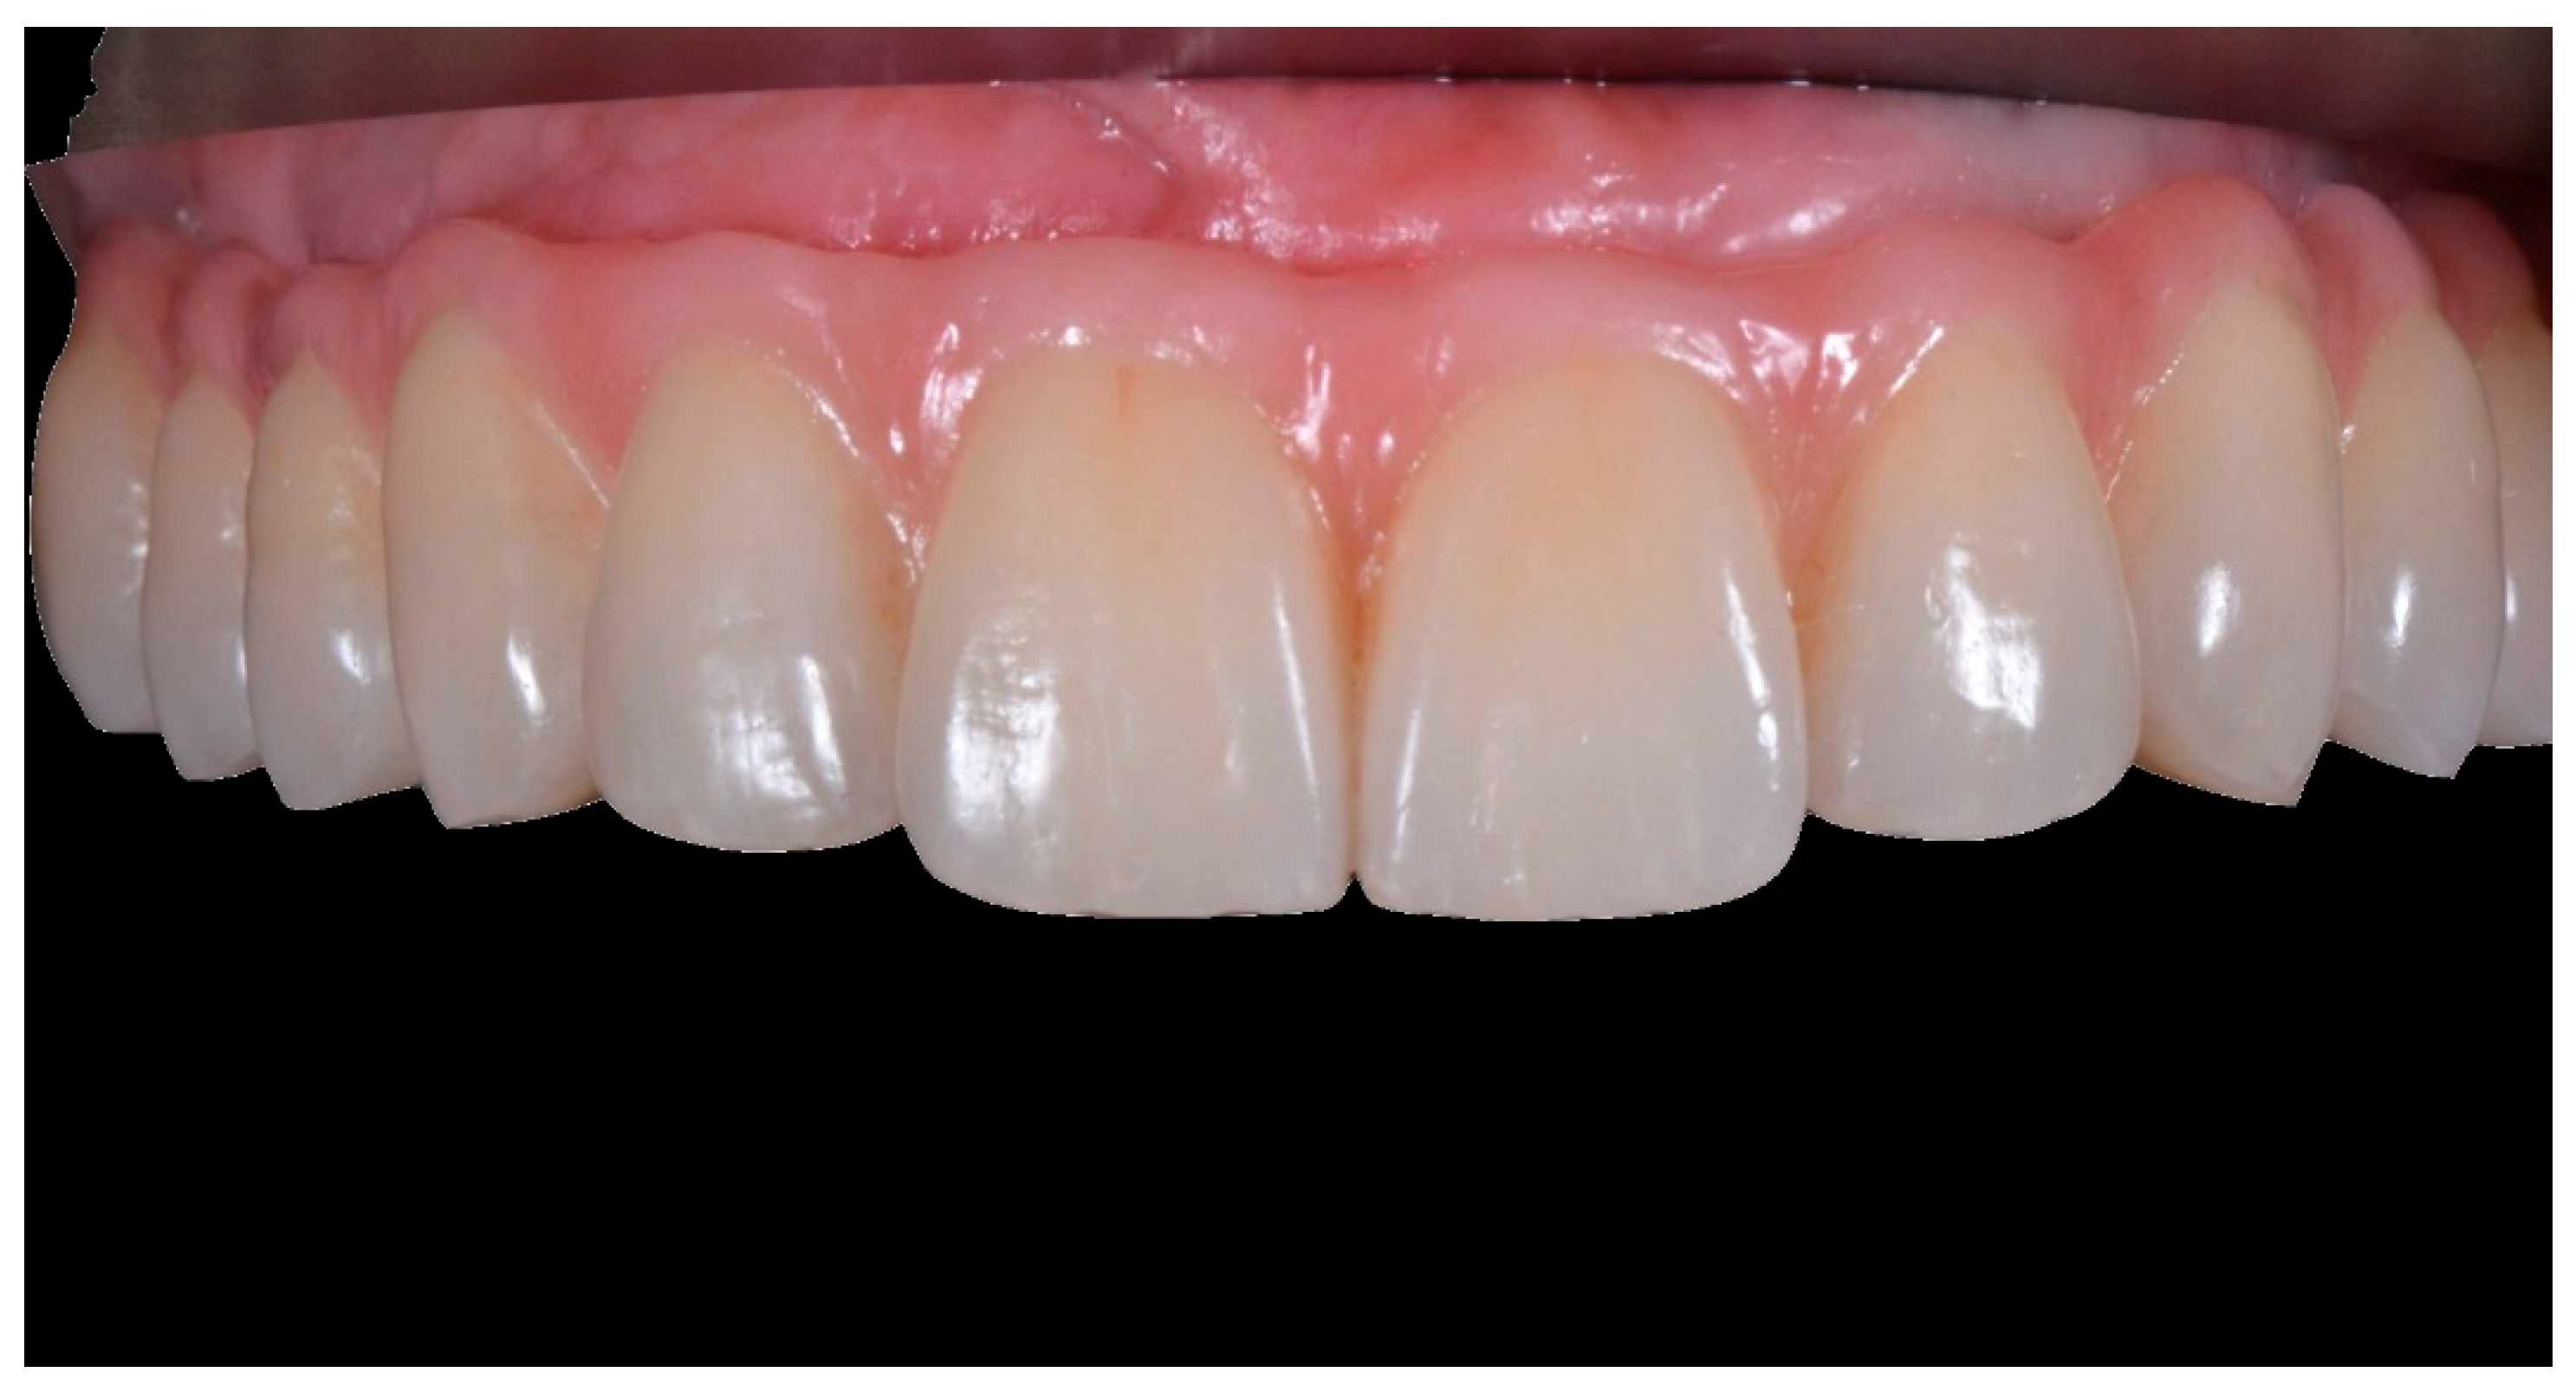

2. Materials and Methods